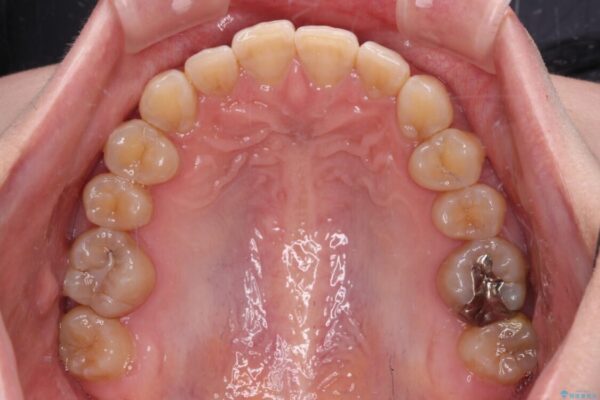

下顎の八重歯を気にして来院された患者様です。

下顎前歯にデコボコが集中していたため、顎間ゴムによる後方移動とIPR(歯と歯の間を削ること)により歯列を整えることとしました。

治療前、下顎前歯のデコボコが集中しており、奥歯の咬み合わせは、上顎に対して下顎が前方位にある状態でした。下顎の歯列を後方へ移動させる治療はインビザラインの得意とするところですので、1年程度で無事に治療を終えることができました。

治療前

• 【モニター】下顎前歯のデコボコをインビザラインできれいに 治療前画像